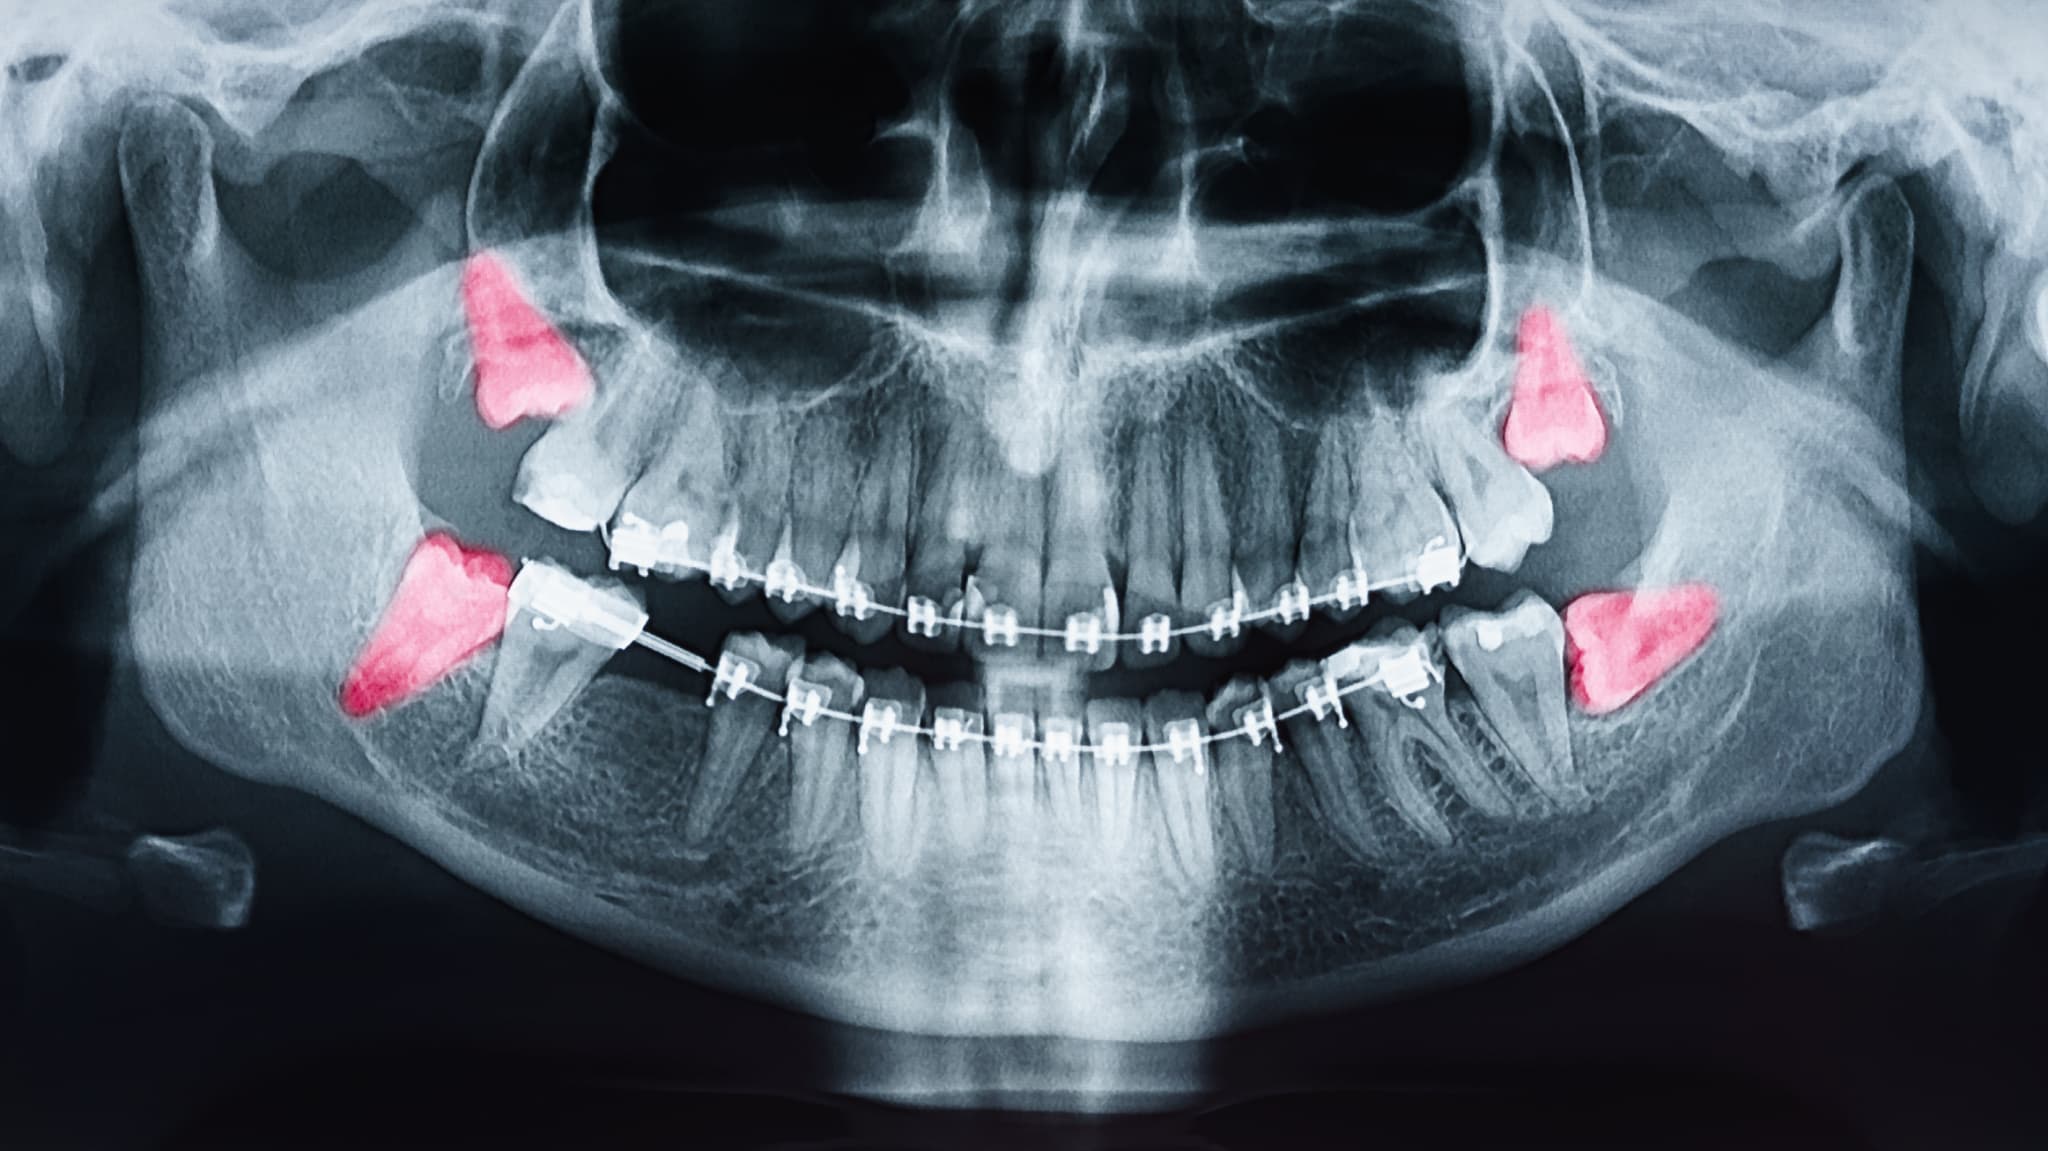

親知らずのレントゲン写真

親知らずとは、永久歯のなかでいちばん奥に生えてくる歯で、正式には第三大臼歯と呼ばれます。前歯から数えて8番目にあたる奥歯で、10代後半から20代前半ごろに生えてくることが多い歯です。上下左右に1本ずつ、合計4本ありますが、人によっては生えてこない場合もあります。

近年は顎が小さい人が増えているといわれており、親知らずが生えるスペースが足りないことも少なくありません。そのため、まっすぐ生えずに斜めや横向きの状態になったり、歯ぐきの一部から少しだけ出てきたりすることがあります。

また、歯ぐきや顎の骨の中に埋まったまま存在しているケースもあります。

見た目ではわからないことも多く、痛みなどの症状がない場合は気づかないまま過ごしている人もいます。そのため、歯科医院でレントゲンを撮ったときに初めて親知らずの存在がわかることも珍しくありません。

親知らずの状態は人それぞれ異なるため、歯科医院で定期的に確認することが大切です。